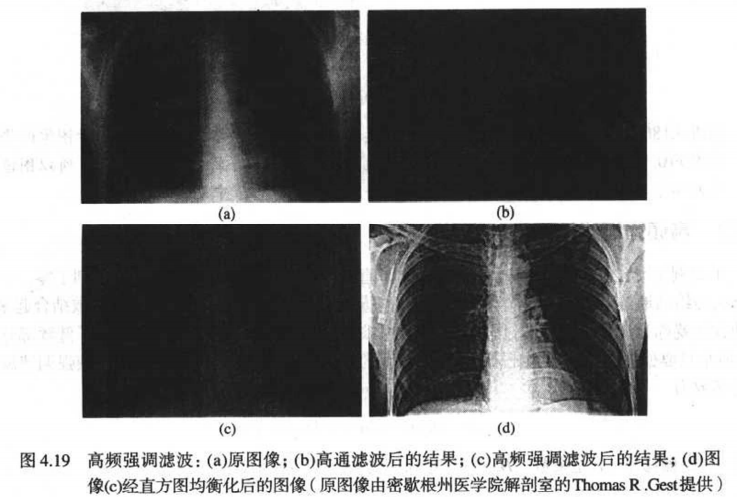

6.2 高频强调滤波

我们可以整体把图片调亮,并且给高通滤波器的传递函数,乘以一个值,让它高通通过的部分更高:

H h f e ( u , v ) = a + b H h p ( u , v ) H_{hfe}(u,v) = a + bH_{hp}(u,v) Hhfe(u,v)=a+bHhp(u,v)

比如当a=0.5,b=2时,书中给出了一组和直方图均衡的对比图: